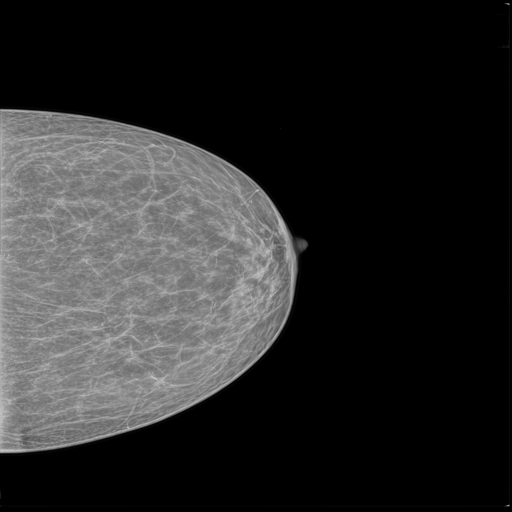

MammoAI revolutionizes breast cancer diagnostics by transforming mammograms into clear, evidence-based reports with actionable next steps. The app addresses critical delays in analysis and limited specialist access, providing faster, clinically informed insights directly from medical imaging and literature.

- Mammogram Upload & Preprocessing – Users can upload images in common medical formats; the app prepares the image for analysis.

- Intelligent Diagnosis & Treatment Reports – Fine-tuned models and LLM-powered agents analyze images and notes, querying specialized medical knowledge bases to generate actionable insights.

- Comprehensive Final Report – Combines mammogram findings, diagnosis, recommended next steps, and practitioner notes into a single, clear report.

Use the following publicly available mammogram images for testing purposes: